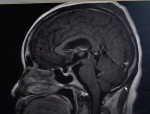

武警广东省总队医院急诊医学科成功抢救呼吸心跳骤停患者

郭静广东记者

21-11-08 11:15

2.4342W+